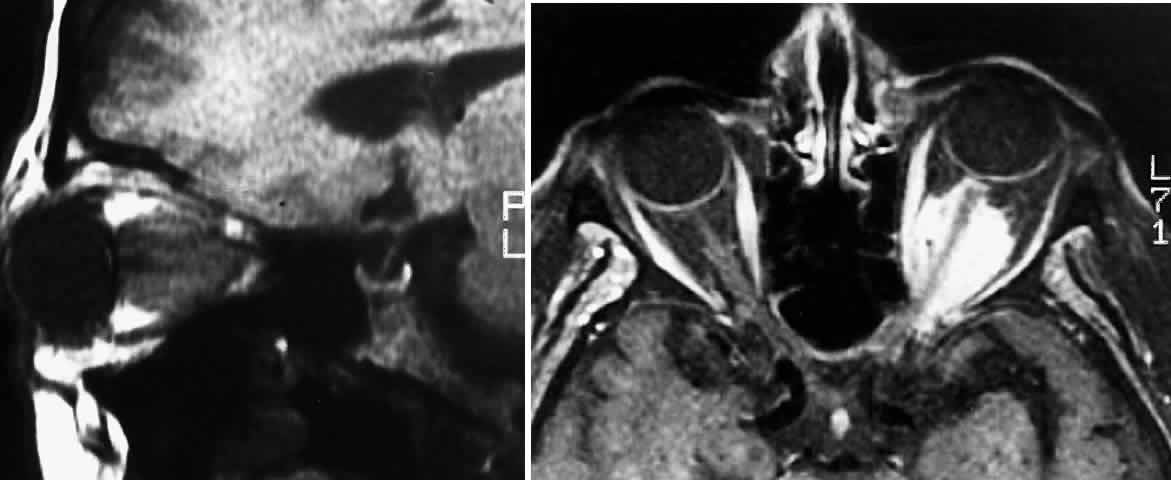

MRI has replaced CT scanning as the optimum test for imaging optic gliomas (Fig. 4 A and B). Optic gliomas have normal to slightly prolonged T1 relaxation times and appear isointense to slightly hypointense to normal brain on T1. Because many of these tumors have prolonged T2 relaxation times, images that are T2 weighted may be used to assess gross tumor margins and posterior extension.72 Optic nerve gliomas often demonstrate minimal enhancement after administration of contrast. To improve MR imaging of optic nerve lesions, a gadopentetate dimeglumine enhancement technique combined with fat suppression can be utilized. Unlike meningiomas, the thickened sheath from arachnoid hyperplasia associated with gliomas will not enhance.77 Although imaging should initially be performed in the axial plane to allow visualization of both the optic nerve and the posterior optic pathways, sagittal views are helpful in demonstrating chiasmal involvement; coronal views can be utilized to delineate intracanalicular tumor.78

Fig. 4. A. T1-weighted sagittal MRI of a patient with neurofibromatosis type 1, demonstrating enlarged optic chiasm consistent with optic glioma. B. T1-weighted coronal image with gadolinium and fat suppression in the same patient, demonstrating the chiasmal glioma.

Fig. 5. A. T1-weighted oblique MRI of the orbit, demonstrating an optic nerve glioma. B. Contrast-enhanced T1-weighted axial MRI of the orbit, demonstrating left meningioma with intracanalicular extension.